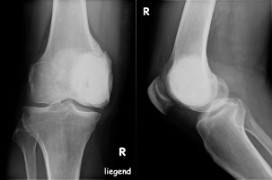

Ursachen Bei Knochentumoren kann meist keine definitive Ursache gefunden werden Gutartige Knochentumore können erblich bedingt sein, die Entstehung bösartiger Tumore kann durch verschiedene Faktoren (z B Strahlung oder Morbus Paget, eine Knochenerkrankung) gefördert werdenDoch meist bleibt es unbekannt, wie bei einem Menschen speziell ein Knochentumor entstanden ist. Frakturen im Kniebereich (oder Kniefraktur) können folgende Strukturen betreffen Kniescheibe, Oberschenkelknorren (auch Femurkondylen genannt) Schienbeinplateau, Knochenfirst am Schienbein (Eminentia intercondylaris) und Schienbeinbeule (Tuberositas tibiae) Die Verletzungen können durch direkte oder indirekte Krafteinwirkung verursacht werdenSchienbein und Kniescheibenbrüche machen 1%. Holly Spraker, MD und Stephen Lessnick MD, PhD Übersetzt von Cornelia Mutz und Heinrich Kovar, PhD Auch in Chinesisch, Englisch, Französisch, Italienisch, Portugiesisch und Spanisch Was ist ESFT?.

Obwohl es schmerzhaft ist, ist es nicht so schwerwiegend wie eine Knieversetzung, bei der Oberschenkelknochen und Schienbein den Kontakt miteinander verlieren Patellasubluxation (instabile Kniescheibe) In diesem Zustand verläuft die Patella nicht gleichmäßig in ihrer Rille am Femur. ArchäologischerJahresberichte 09 Dienst Graubünden des Archäologischen Dienstes Graubünden und Denkmalpflege Graubünden der Denkmalpflege Graubünden Jahresberichte 09 Poschiavo, Oratorio S Anna Anthropologische Untersuchungen Christina Papageorgo poulou, an den neuzeitlichen Schädeln aus dem Beinhaus Frank Siegmund, Geraldine d’Eyrames, Viviane Roth, LK 1278, 801 713/133 860. Informieren Sie sich über die Ursachen von Knieschmerzen, die von Bänderverletzungen bis zu Arthritis und Bursitis reichen, und erfahren Sie, wie Ärzte die Kniediagnostik behandeln.

Obwohl es schmerzhaft ist, ist es nicht so schwerwiegend wie eine Knieversetzung, bei der Oberschenkelknochen und Schienbein den Kontakt miteinander verlieren Patellasubluxation (instabile Kniescheibe) In diesem Zustand verläuft die Patella nicht gleichmäßig in ihrer Rille am Femur.